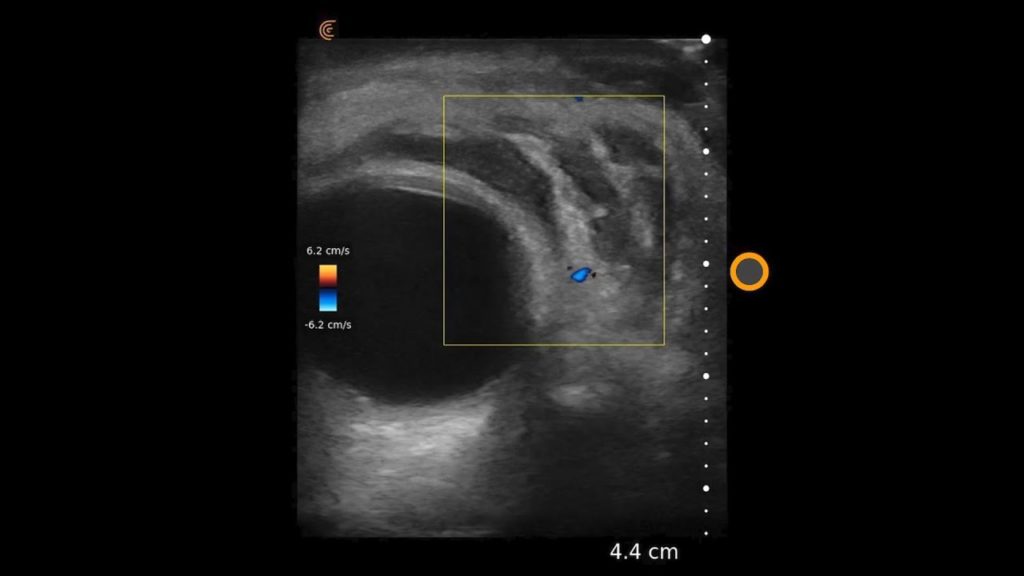

Using the jejunum as an important landmark, the hypoechoic jejunal lymph nodes can be identified. In this video Dr. Edwards explains the ultrasound appearance of normal jejunal nodes.